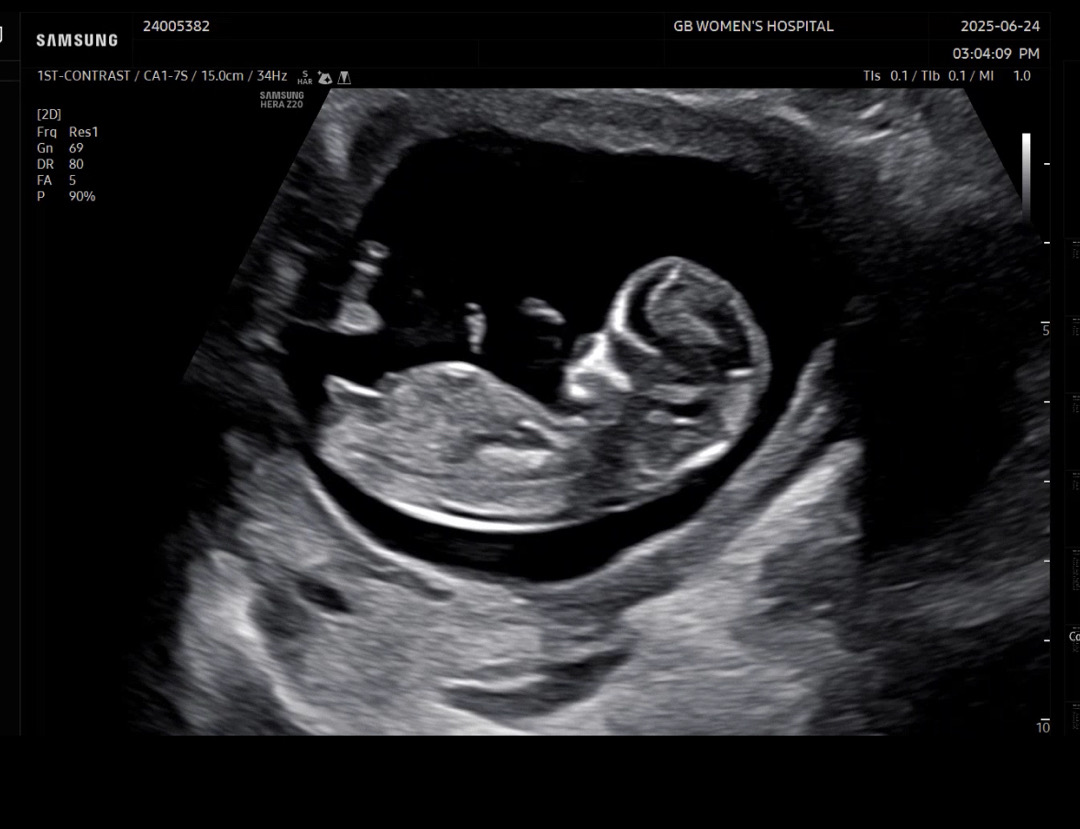

성별 확인 부탁드려요 💛

각도법 성별 확인 부탁드려용 💛

딸이네요!!!

딸 같아요~!!

딸 같아요!